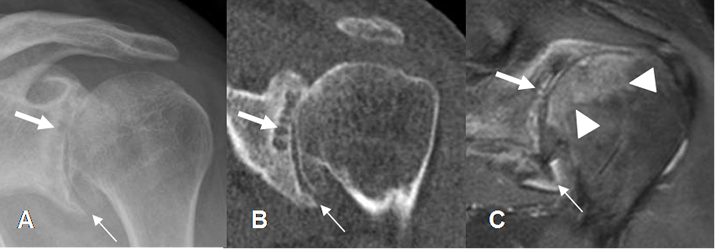

Fig 89. Pinzamiento interno anterior.

A: Rx AP. B: TAC reconstrucción coronal y C: RM coronal en STIR. Cambios degenerativos con pérdida del espacio glenohumeral, formación de osteofitos inferiores (Flechas delgadas), quistes subcondrales (Flechas gruesa) y edema óseo en la cabeza femoral, por microtrauma (Punta de flecha.).